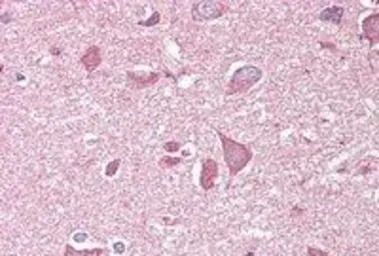

IHC-P analysis of human cortex using GTX89311 NCAM2 antibody, C-term.

Antigen retrieval : citrate buffer pH 6

Dilution : 3.75μg/ml